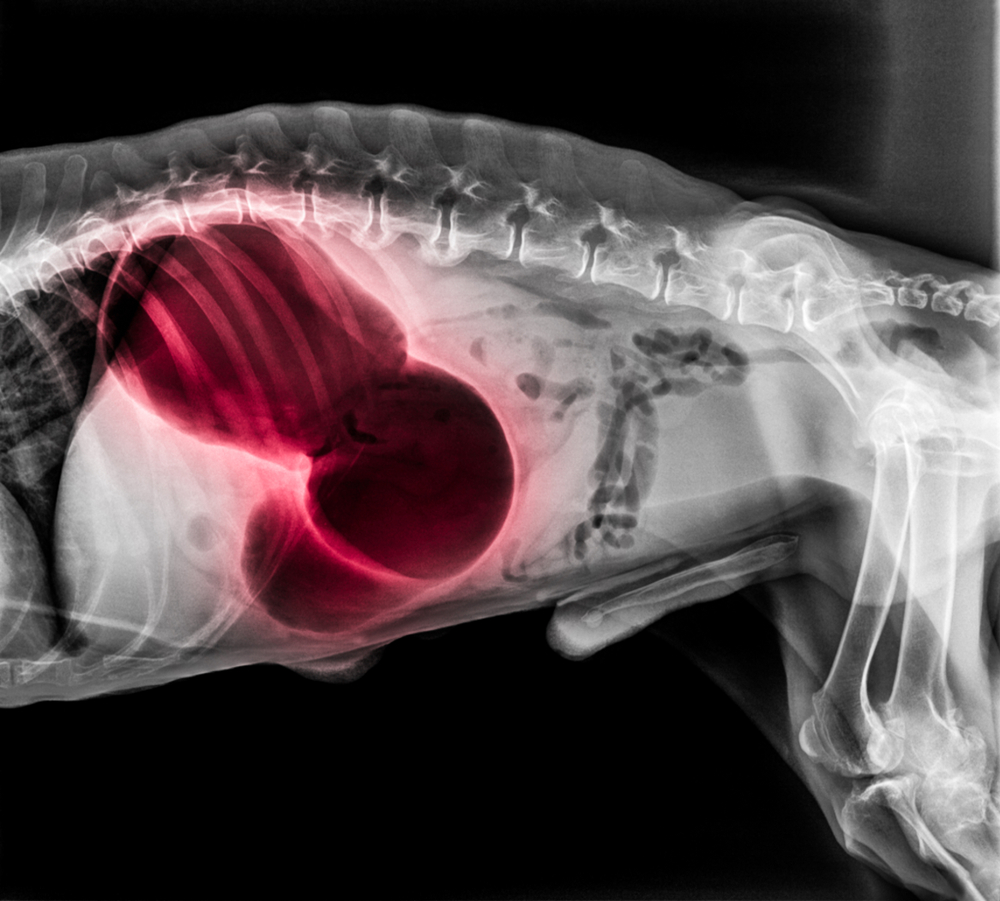

Bloat is an acute-onset condition where a dog’s stomach distends or fills with gas. In some cases the condition does not progress beyond this, but unfortunately, bloat can quickly become more serious. Bloat can lead to a condition known as gastric dilatation-volvulus (GDV) complex or stomach torsion. In this case, the stomach not only fills with gas, but then twists, blocking both its entrance and exit. As the stomach presses on the diaphragm, breathing may become difficult. The veins that carry blood to the heart are compressed, reducing blood flow and causing an affected dog to go into shock. If you see signs of bloat, you should treat it as a medical emergency - GDV can be fatal within an hour.

Emergency treatment involves stabilizing the dog, addressing any signs of shock, and decompressing the distended stomach (either by placing a device called a trochar into the stomach through the abdomen or passing a tube down the esophagus into the stomach). X-rays are used to determine if the stomach has twisted.

If a dog has GDV, surgery must be performed as soon as the dog is stabilized. Surgery will return the stomach to its proper positioning and remove any dead tissue. If the spleen is damaged it may also be removed. In many cases, a gastropexy is also performed. Gastropexy is a surgery that can permanently fix a dog’s stomach into place, preventing future episodes of GDV.